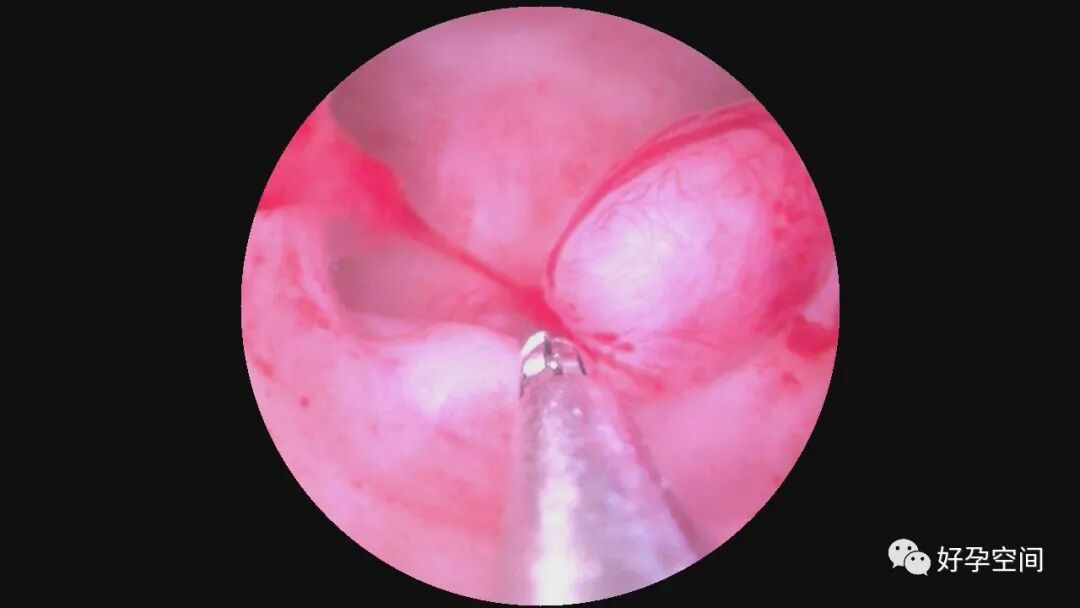

病例3:30岁,G3P1,顺产1次,孕12周胚胎停育1次并清宫,本次停经9+周,稽留流产。一次性宫腔镜见宫颈管下段息肉,约2.0*1.0*0.8cm,胚胎着床于宫腔下段后壁,不规则,张力差,摘除胚胎、切除息肉后见宫腔左侧粘连,切除粘连,宫腔形态正常,双侧输卵管开口可见。